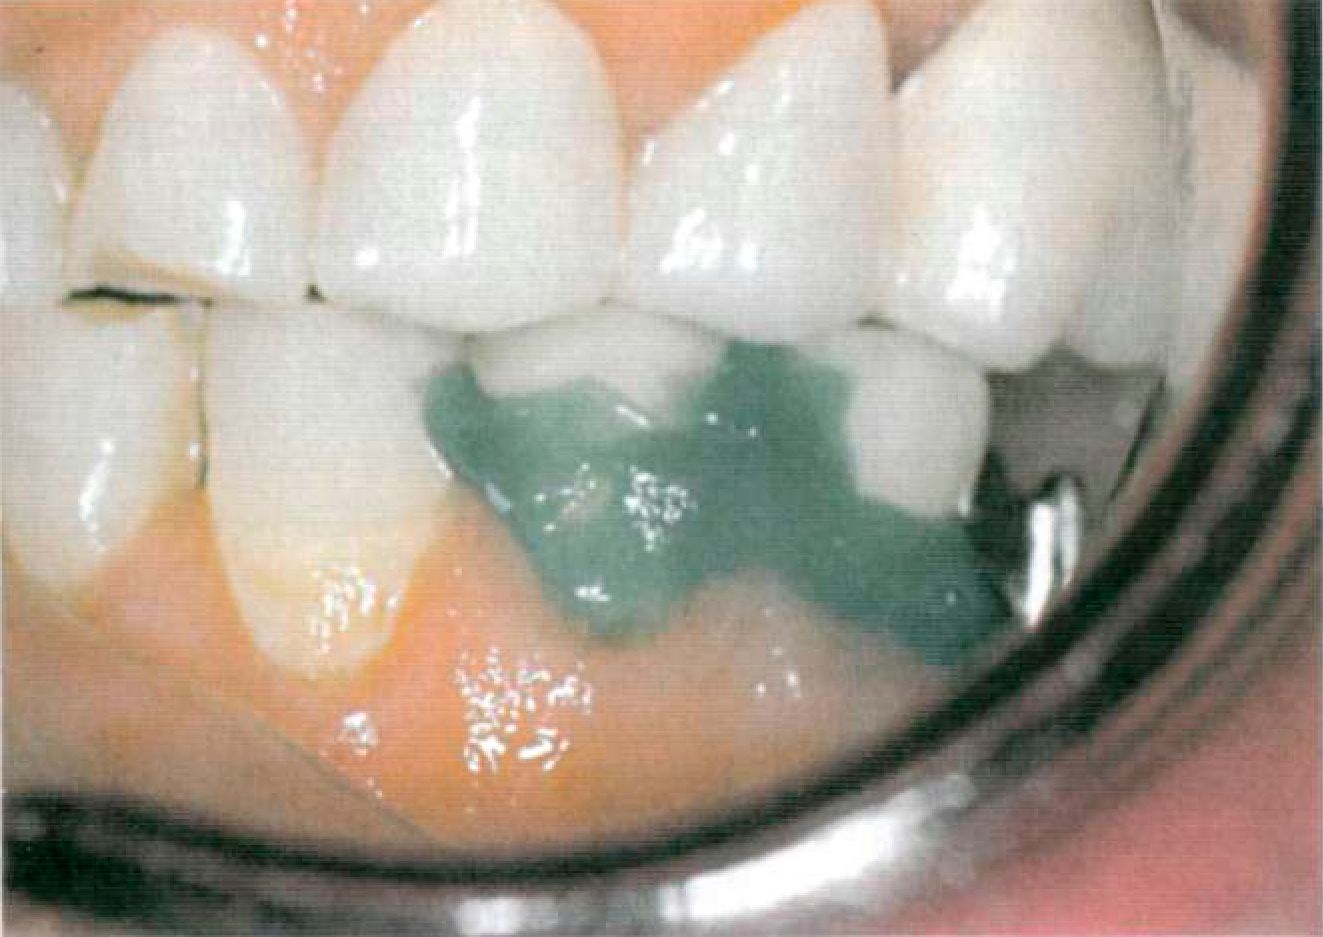

Этап 5. После нанесения зубным техником керамической облицовки в клинике проводят припасовку металлокерамических коронок опорных зубов (рис. 109). Выверяют окклюзионные контакты, цвет. Этап 6. После глазуровочного обжига коронки фиксируют в полости рта на корригирующий оттискной материал для избежания смещения (рис. 110) и снимают оттиск для изготовления съемной части комбинированного протеза. Возможно применение индивидуальной ложки, изготовленной по предварительному альгинатному оттиску. Опорные коронки с замковыми креплениями переходят в оттиск (рис. 111). Этап 7. В лаборатории опорные коронки заливают воском и по полученному оттиску изготавливают рабочую модель (рис. 112). К замковому креплению, установленному на опорных коронках, присоединяют комплементарную часть (рис.113) или ее аналог. В зависимости от типа замкового крепления и конструкции съемной части протеза модель дублируют или проводят моделировку каркаса на рабочей модели, используя беззольную пластмассу (рис. 114).